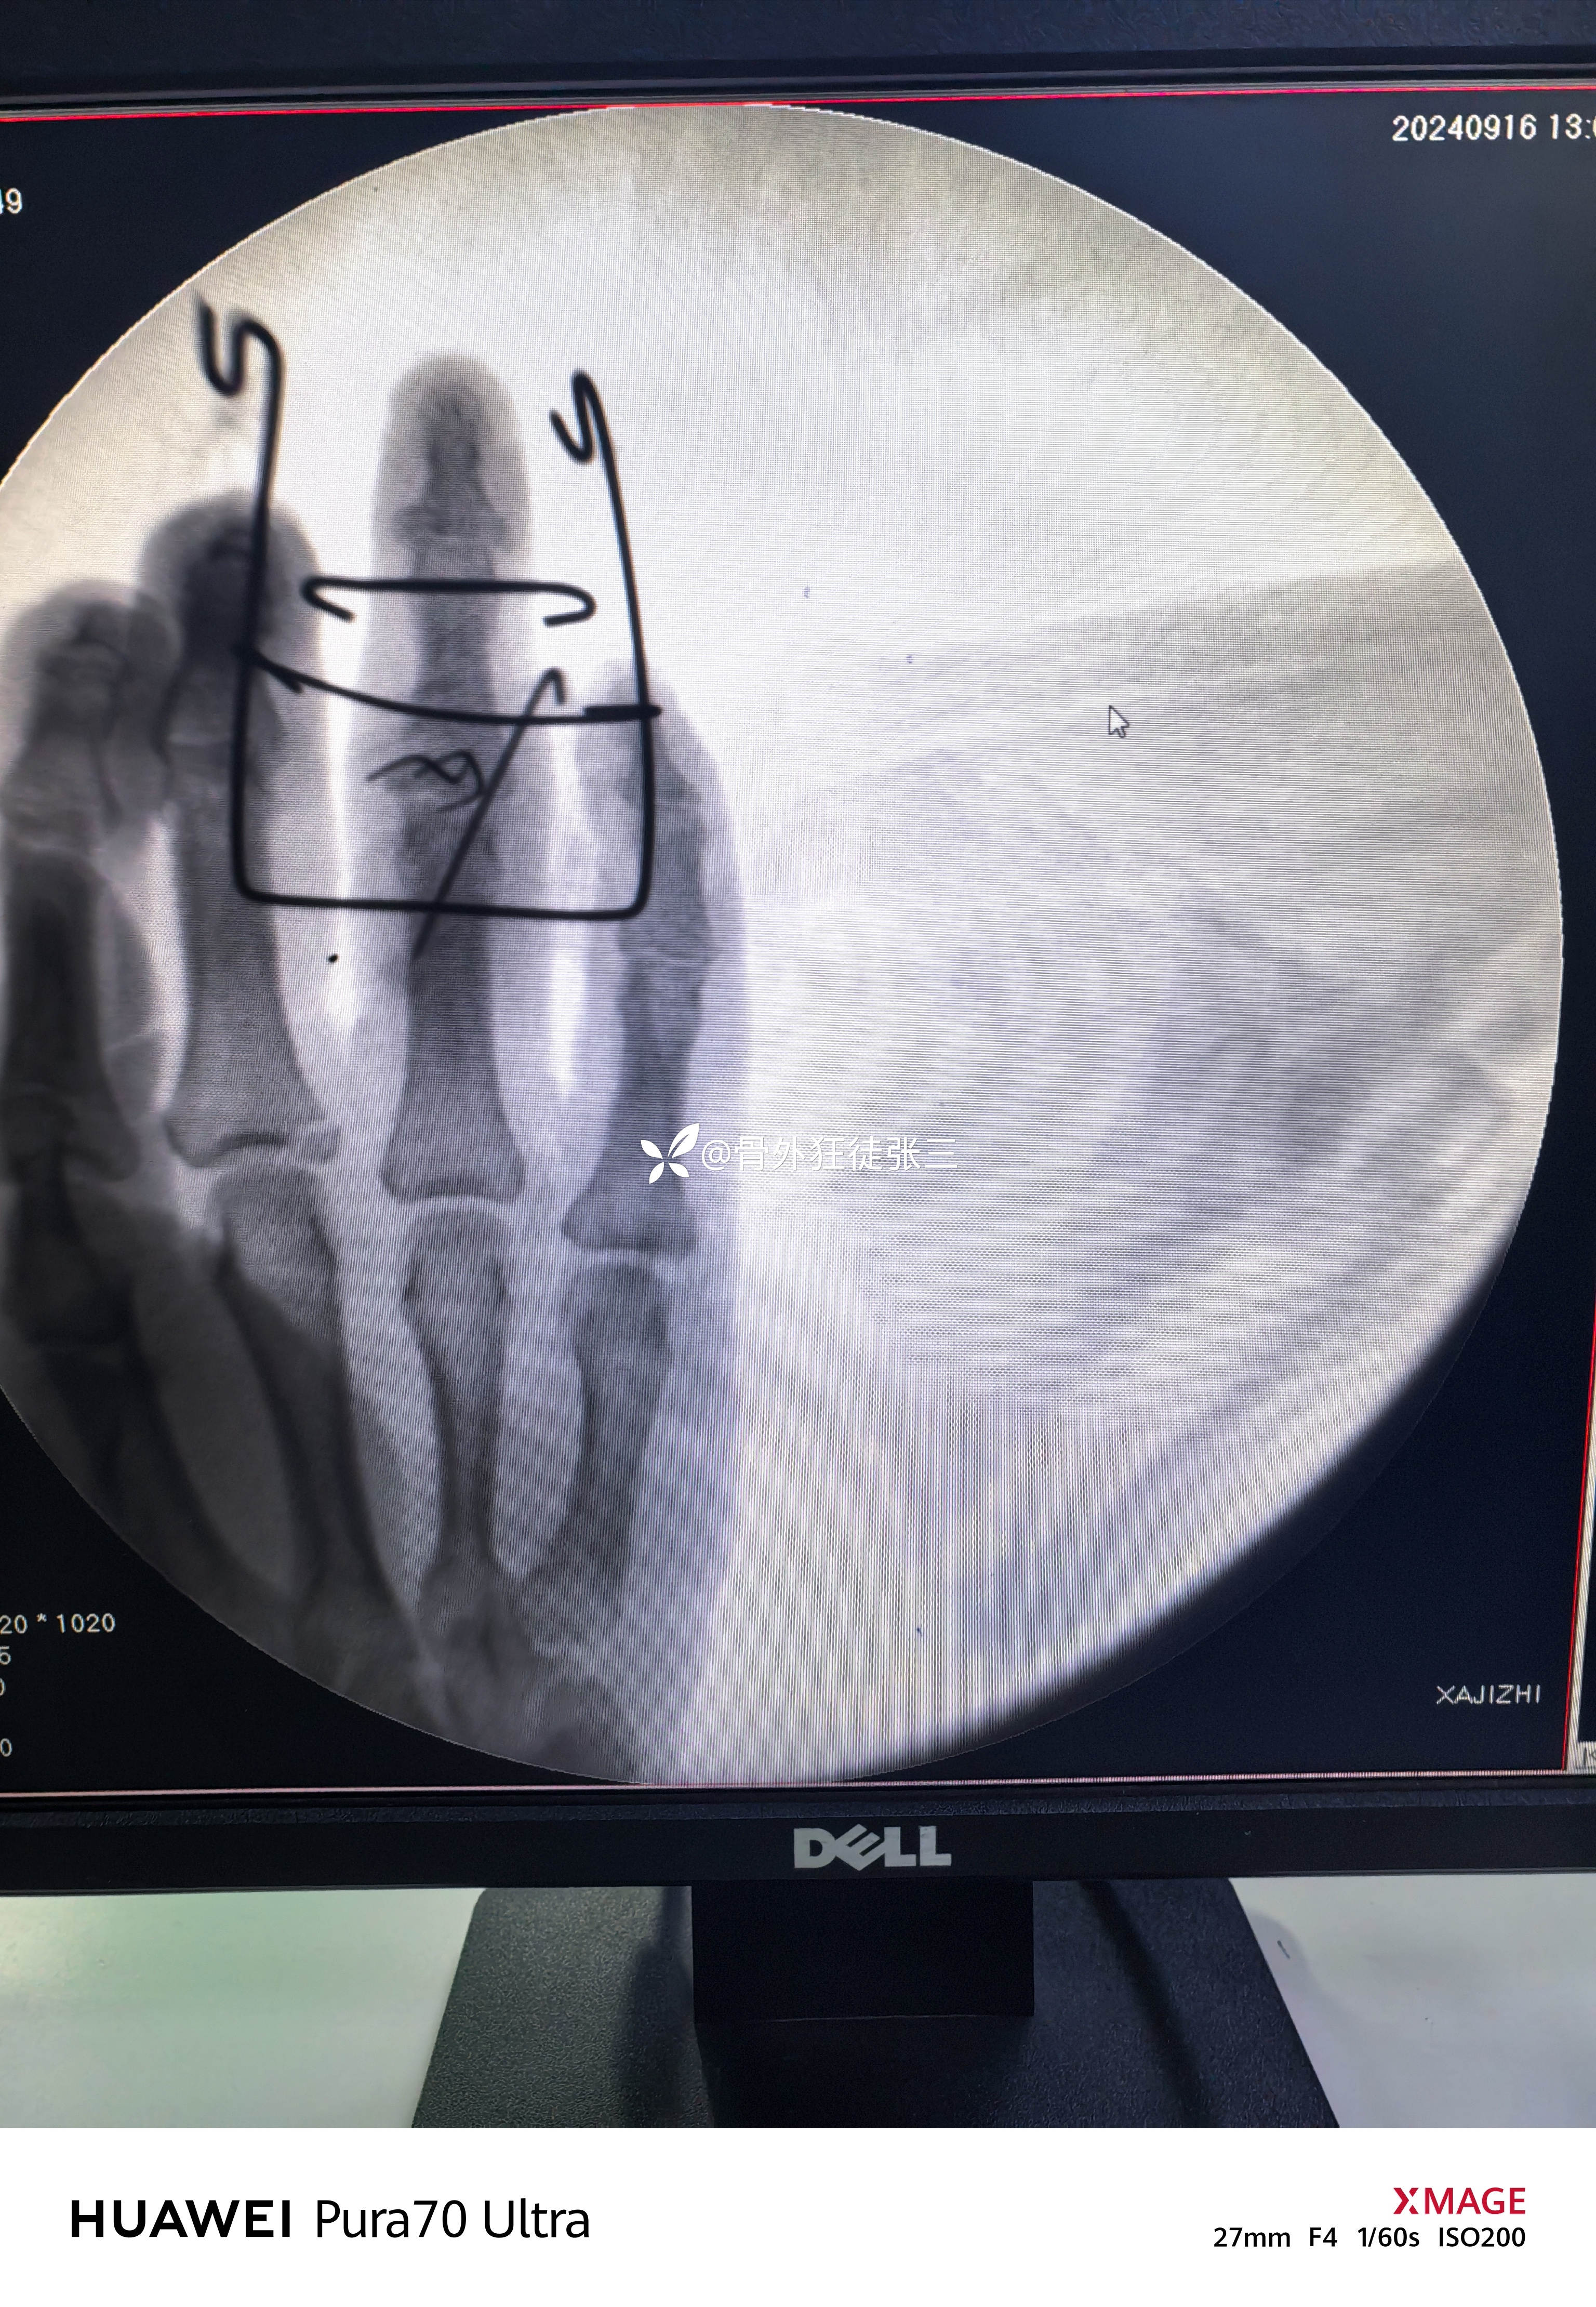

透视发现骨块复位

关节复位

五,术后处理

1,弹力带持续牵引

2,关节部位的克氏针固定3周

3,3周后开始动态牵引下功能锻炼

4,4+6周复查X线,愈合后拔针。

5,术后定期随访,若出现创伤性关节炎,再次融合或者人工关节置换。